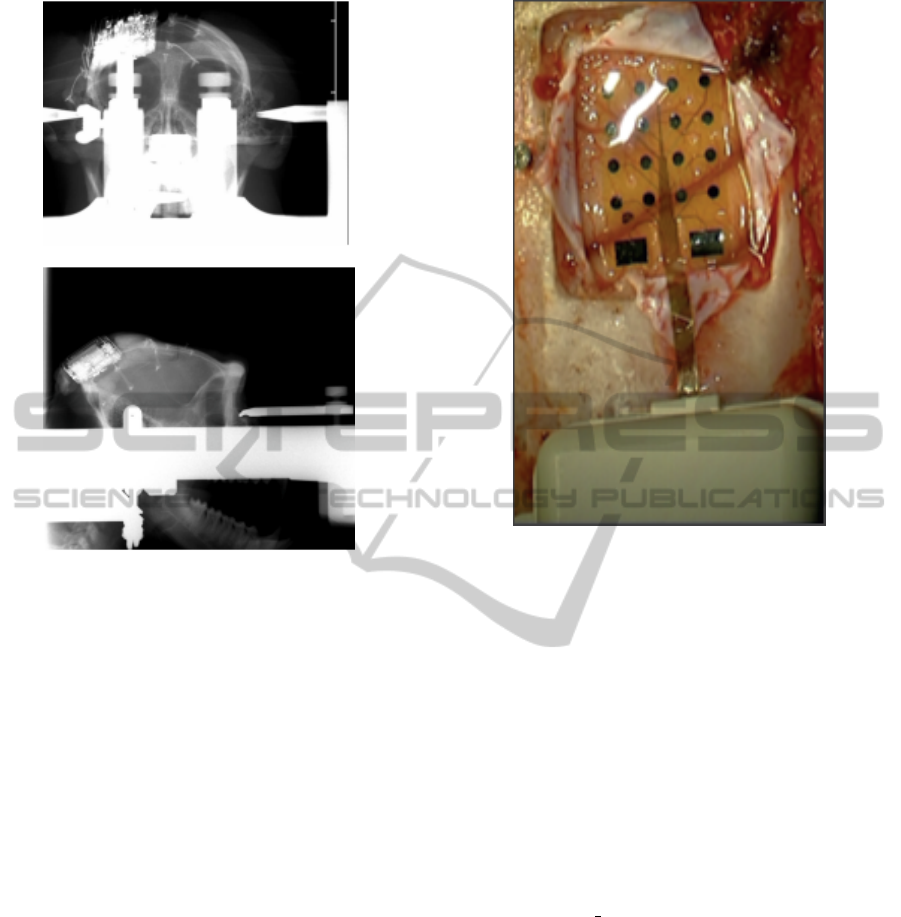

The implantable wireless device, here presented, al-

low us to perform chronic EcoG recording and DCS.